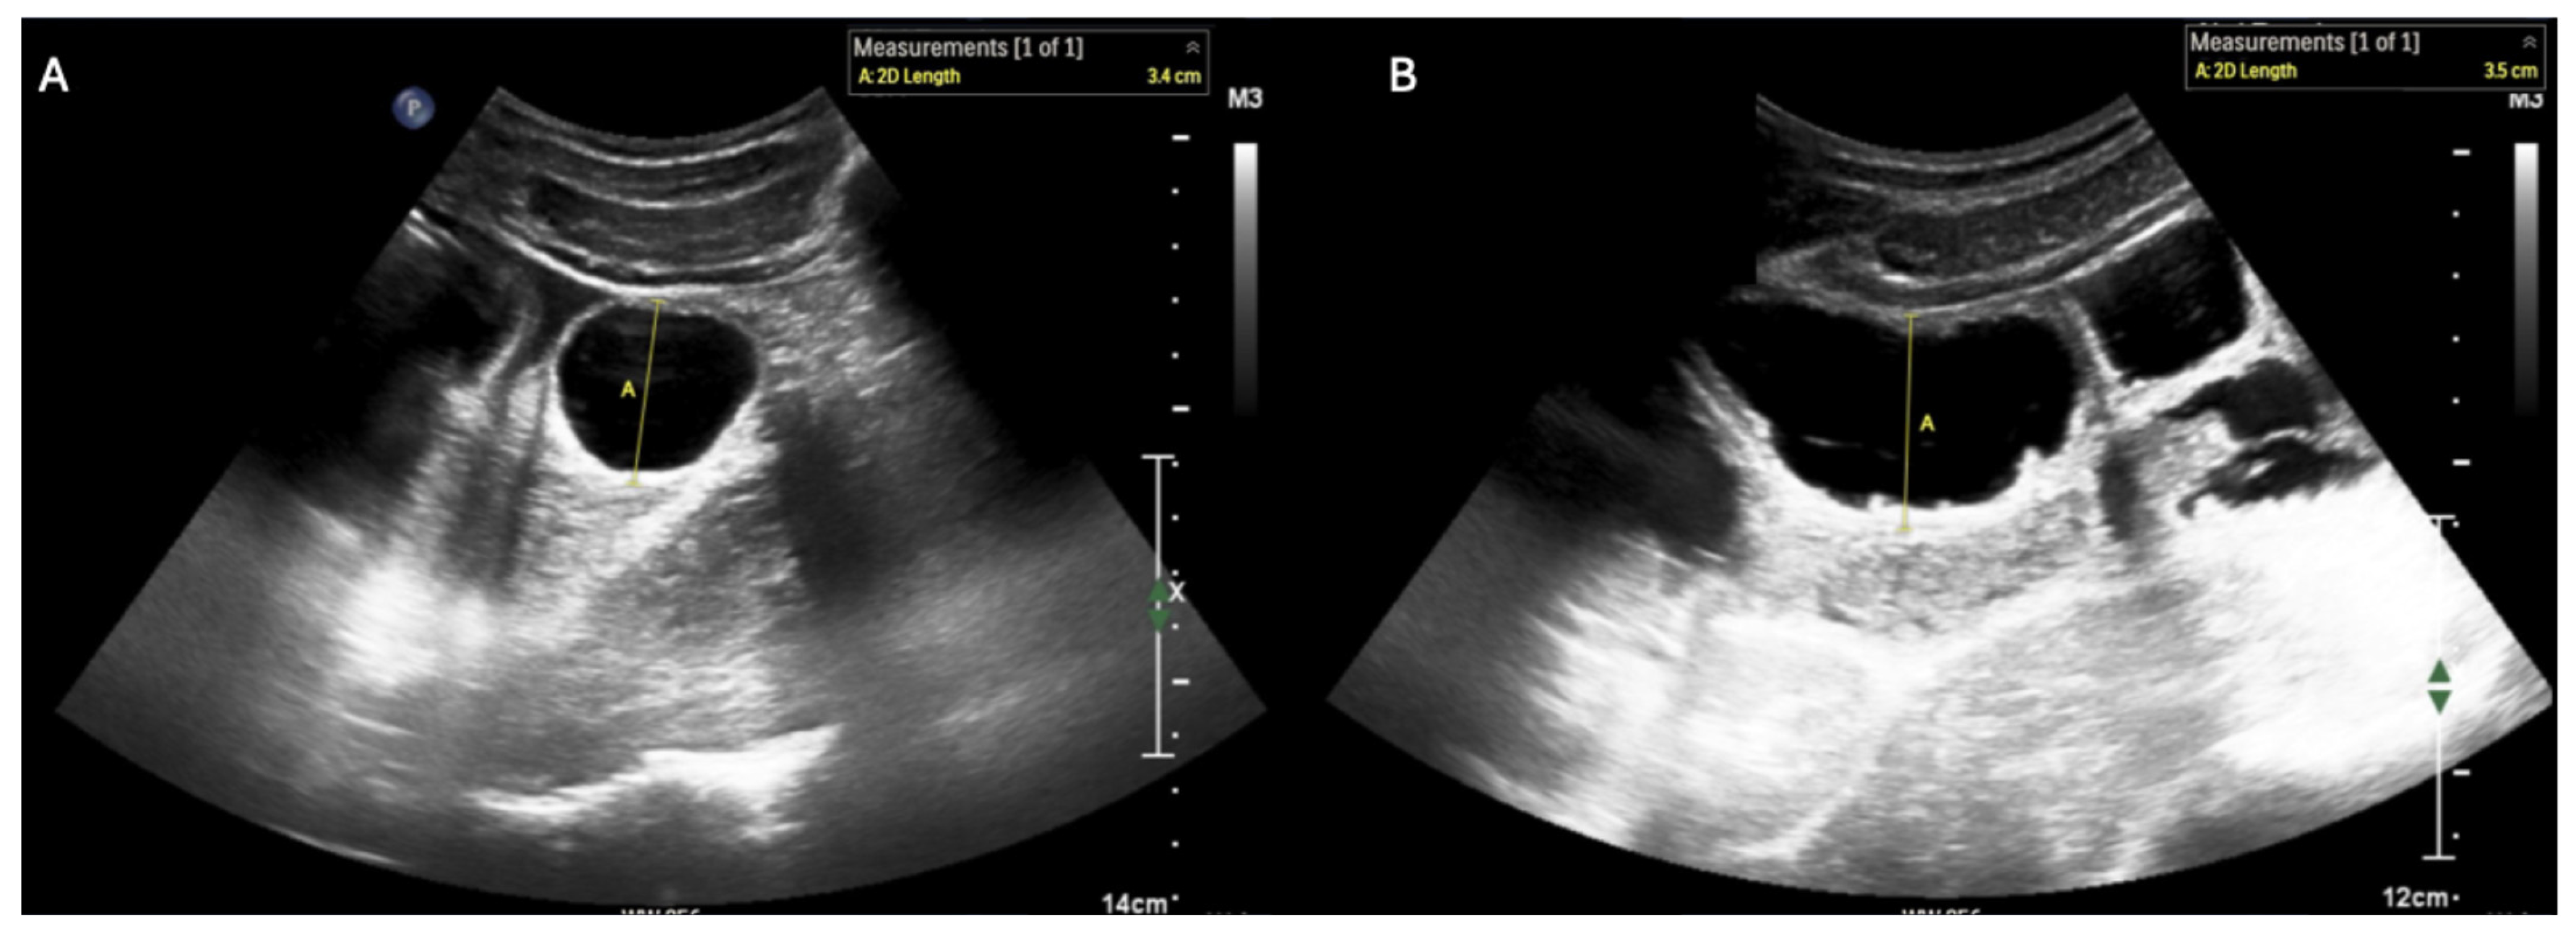

Short- (A) and long-axis (B) views of small bowel ileus, which has the following characteristics on ultrasound: (i) small bowel outer wall to outer wall diameter ≥ 2.75 cm (with 2.5–2.75 cm representing a borderline value) [8] and (ii) absent peristalsis [10]. Abnormal peristalsis is characterized either by (a) a complete absence of motion of intra-luminal contents or (b) “to-and-fro motion” of the bowel contents with a minimal decrease in size of the small bowel lumen (see Supplementary Video S3 for examples of these dynamic findings) [11].